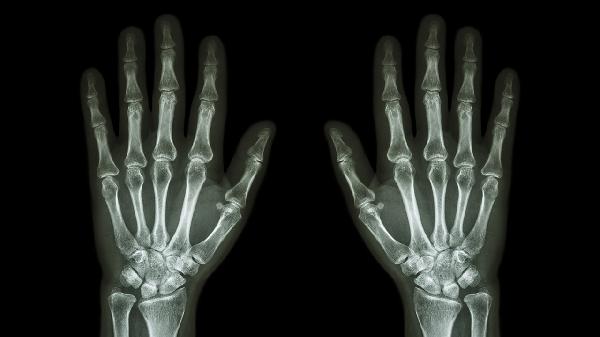

手背指关节发黑是什么原因

手背指关节发黑可能与色素沉着、外伤、血液循环障碍、代谢性疾病、药物因素等原因有关。建议及时就医明确诊断,针对性处理。